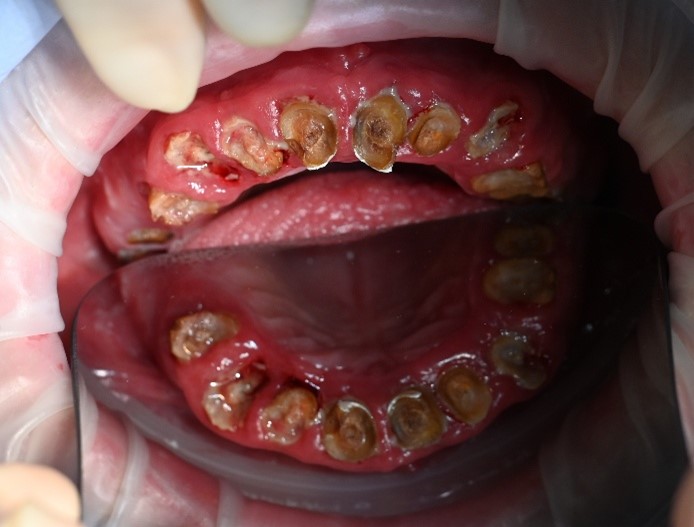

We completed a full clinical examination and took detailed records, including:

• clinical photographs

• intraoral photos

• OPG x-ray

• CBCT scan

• digital implant planning records

These records helped us carefully assess bone levels, gum health, and implant positions.

xAlthough the patient had moderate bone loss in some areas and signs of old chronic abscesses, his overall bone quality was still suitable for implants. There was no active pus or severe infection at the time of treatment.